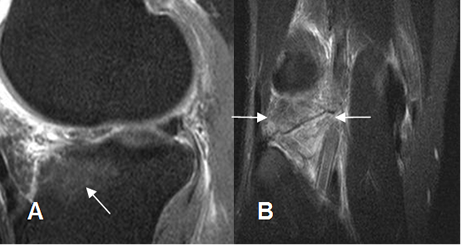

Fig 124. Ruptura del LCL.

A: RM coronal en T1 y B: RM coronal en STIR. No visualización del LCL, por ruptura. Igualmente hay lesión de la banda iliotibial. (Flecha delgada).